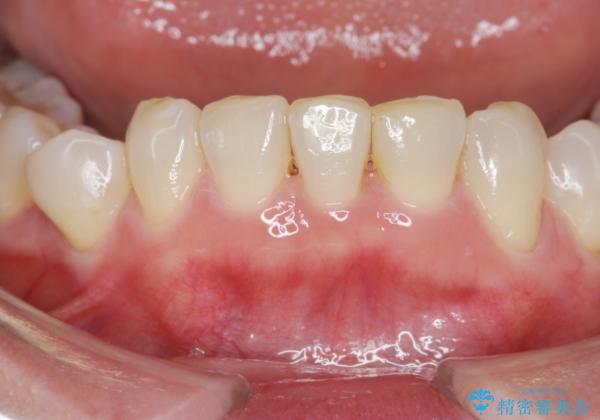

インビザラインで行う前歯のみの部分矯正

- 長年気になっていた前歯の歯並びを改善したいと、矯正治療を希望され思い切って来院されました。

費用と期間を相談し、「気になっているのは前歯だけ。」とのことでしたので前歯のがたつきのみをインビザラインで改善する矯正治療の計画を立てます。

しっかりとマウスピースの装用時間を守っていただき、非常にスムーズに治療を終了することができました。